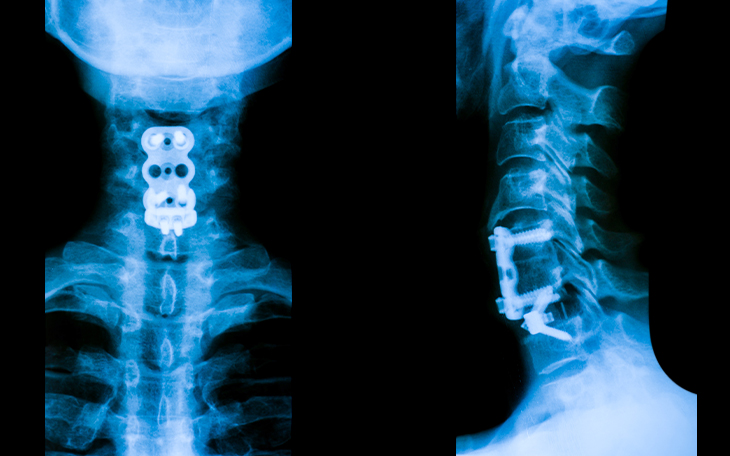

Bildquelle: www.docset.de

• ACDF (vordere Halswirbelsäulenoperation): Entfernung der Bandscheibe und Versteifung mit Cage und ggf. Metallplatten

• ACDR (Bandscheibenprothese): Implantation bei jungen Patienten ohne fortgeschrittene Arthrose

• Minimal-invasiv: Hintere Dekompression (Foraminotomie), wenn keine Versteifung notwendig ist

• ventral (von vorne) Spondylodese (z. B. ACDF)

• kombiniertes Vorgehen von vorne und hinten (360° Stabilisierung)